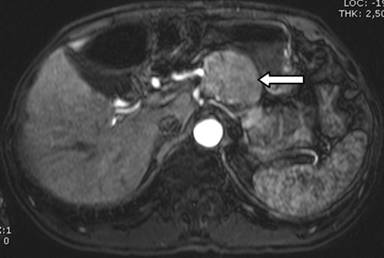

A 64-year-old male with a six-month past history of asthenia, adynamia, and lack of general clinical conditions that leads him to a 13 kilograms weight loss. Also, during this period he refers lypotimic episodes, sporadic diarrheal symptoms without cause, lower limbs muscle pain and extremities paresthesia (hands). The patient is a heavy smoker and he reveals drinking in social events on weekends. On physical examination he had regular clinical state, weight loss signs are present and no palpable masses or adenopathies are revealed in the abdominal examination. Laboratory blood tests results showed a hemoglobin level of 9.7 g/dL (reference range: 12.4-14.9 g/dL), sodium and potassium of 135 mmol/L (reference range: 137-148 mmol/L) and 4.8 mmol/L (reference range: 3.5-5.0 mmol/L), respectively. Normal alkaline phosphatase of 170 U/L (reference range: 50-250 U/L) with abnormal gamma glutamyl-transpeptidase of 87 U/L (reference range: 2-30 U/L) and confirming an extreme malnourishment, albumin value of 1.8 g/dL (reference range: 3.2-5.6 g/L). HCV and HBV serologic results were negative and also tumor markers CEA and CA 19-9 were non-conclusive. Imaging studies were made and the abdominal ultrasound showed a nodular hypoechoic mass in the pancreatic head, with precise delimitation boundaries and dimensions of 5.07x4.17 cm. Abdominopelvic CT scan showed an expansive formation in the head of the pancreas of 5.1x6.1 cm between the lesser gastric curvature and the pancreas head, with no cleavage point with this structure, with homogeneous signal and a “wash-out” delay appearance. Other portions of the pancreas were normal and no ductal distortions were seen; he also had bilateral renal cysts. Magnetic resonance imaging showed a 5.5x4.5 cm mass arising from the pancreatic body in close relation to the celiac trunk, without pancreatic duct dilation, low signal reperfusion signs in the spleen and the already described renal cysts (Figure 1). The patient developed an exacerbated worsening of clinical conditions associated to an acute renal insufficiency which led him to our institution’s emergency room. After his clinical recovery and under a pancreatic tumor of undefined etiology hypothesis, surgery was indicated. Access was made through a subcostal bilateral incision. Upon entering the lesser sac and exposing the pancreas, we found a well delimited exophytic mass, with fibroelastic consistence in the superior aspect of the pancreatic transition between the head and the body of the pancreas (Figure 2). Enucleation of the lesion was performed (Figure 3). Final pathology report of the tumor was hyaline vascular variation of Castleman’s disease. Strepto24 avidin-biotin-peroxidase immunohistochemistry were positive for CD20, CD45RO, CD34 in vessels and Epstein-Barr virus positive.

Figure 1. Magnetic resonance imaging showed a 5.5x4.5 cm mass arising from the pancreatic body (white arrow). |